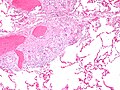

Sarcoidosis-like granulomas in a lymph node. H&E stain. | |

| LM | well-formed granulomas often with few surrounding lymphocytes ("naked"), usually non-necrotizing |

- Granulomata, well-formed, non-necrotizing. ‡

- Usu. minimal (lymphoid) inflammation; sarcoid granulomas are known as "naked granulomas".[8][1]